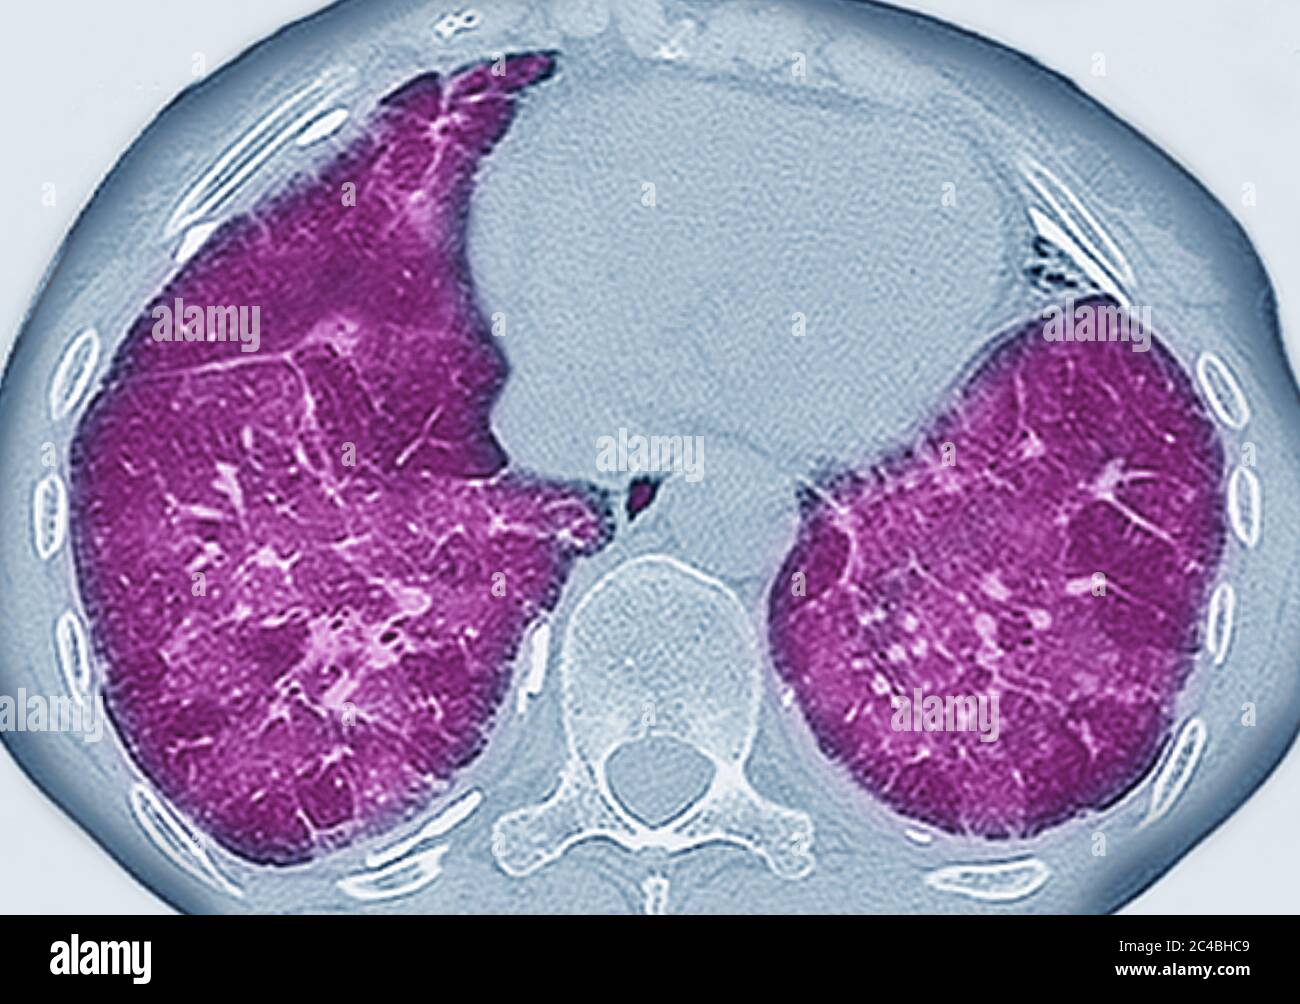

Pulmonary fibrosis (lesion of the lungs characterized by the presence Mixed Connective Tissue Disease Lung Fibrosis This approach is similar to therapy for myositis. Interstitial lung disease (ild) has now become a major cause of morbidity and mortality of patients with connective tissue diseases (ctds). This review aims to collate current evidence on the screening, diagnosis, and treatment of various connective tissue disease. The spectrum of pulmonary manifestations associated with mixed connective tissue disease ranges from. Mixed Connective Tissue Disease Lung Fibrosis.

Connective tissue diseaserelated pulmonary fibrosis showing anterior Mixed Connective Tissue Disease Lung Fibrosis It has been associated with higher. Mixed connective tissue disease (mctd) is an autoimmune disease first described by sharp et al in 1972, characterized by the presence of anti. Interstitial lung disease (ild) has now become a major cause of morbidity and mortality of patients with connective tissue diseases (ctds). This approach is similar to therapy for myositis. Pulmonary manifestations. Mixed Connective Tissue Disease Lung Fibrosis.

Connective tissue diseaserelated pulmonary fibrosis showing anterior Mixed Connective Tissue Disease Lung Fibrosis The spectrum of pulmonary manifestations associated with mixed connective tissue disease ranges from pulmonary. Interstitial lung disease (ild) has now become a major cause of morbidity and mortality of patients with connective tissue diseases (ctds). This review aims to collate current evidence on the screening, diagnosis, and treatment of various connective tissue disease. It has been associated with higher. Pulmonary. Mixed Connective Tissue Disease Lung Fibrosis.